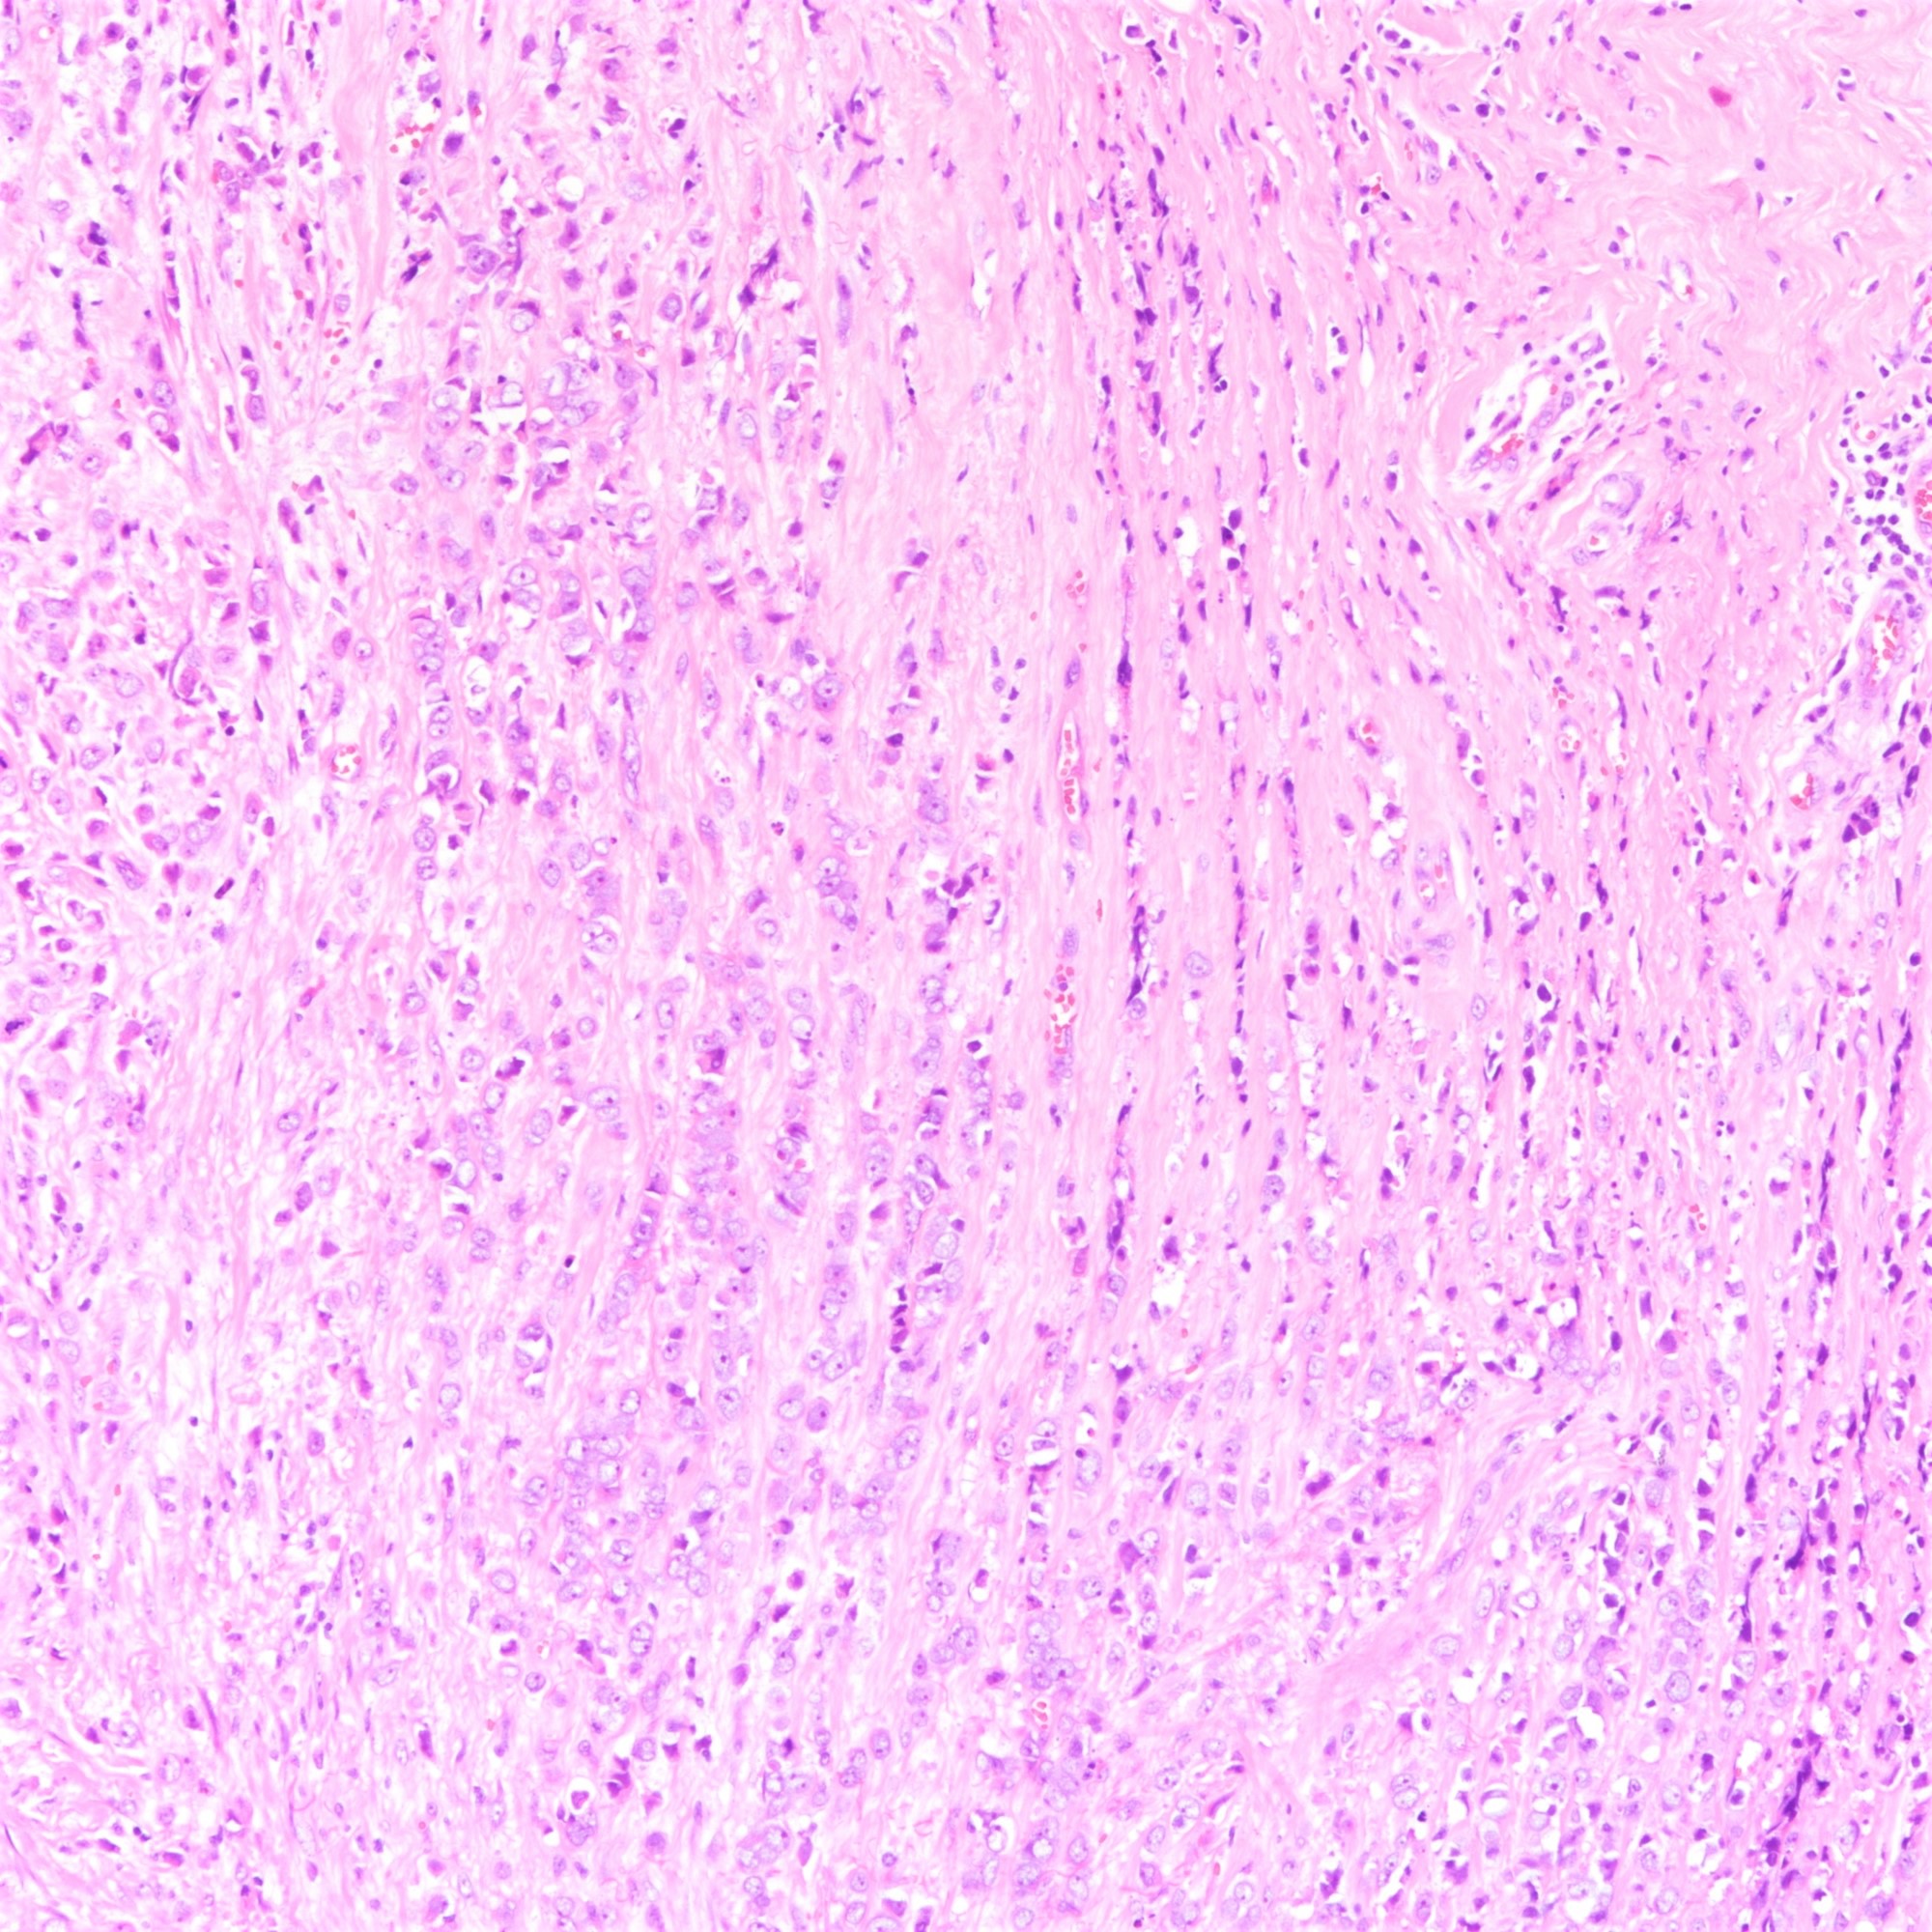

Microscopic (histologic) description

- Tumor cells arranged in single files, cords and single cells (Breast Cancer Res 2015;17:12)

- Can be arranged concentrically around normal ducts, giving a targetoid appearance

- Tumor cells discohesive, small, monomorphic and lacking marked atypia

- Round or notched ovoid nuclei, usually grade 1 or 2 nuclear score

- Scant cytoplasm, occasional with intracytoplasmic lumen

- Mitosis infrequent

- Desmoplastic reaction and necrosis uncommon

Microscopic (histologic) images